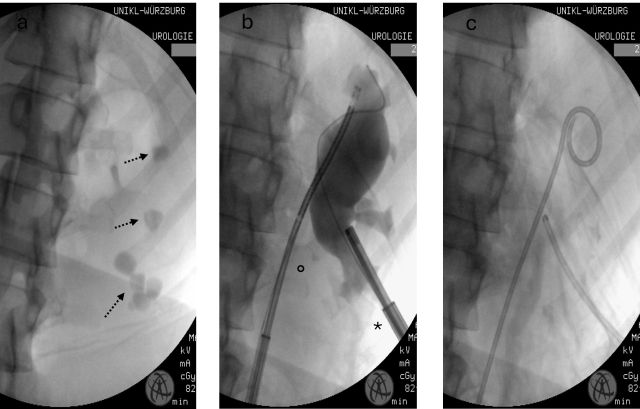

Uniklinikum Würzburg: Laser löst Nierensteine auf